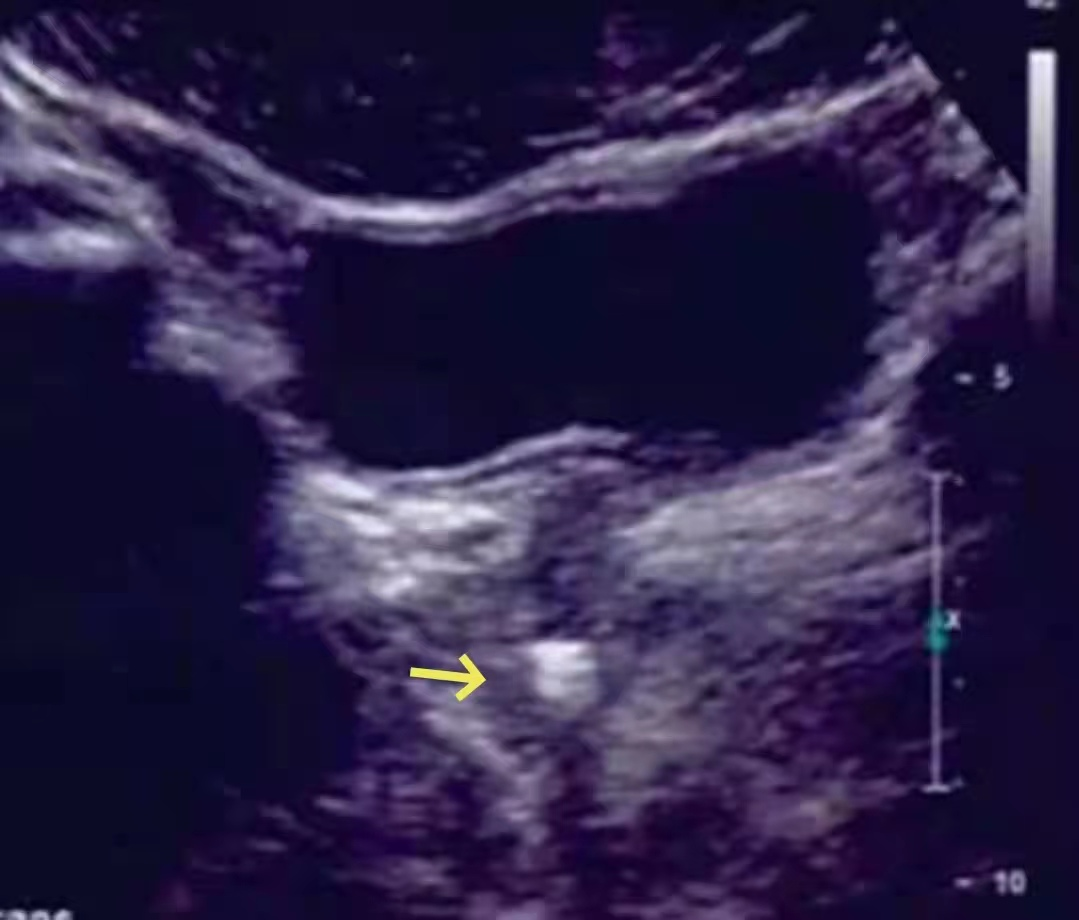

不知道大家有没有碰到过这种情况:患者因为排尿困难、尿线变细前来就诊,门诊行彩超检查提示前列腺部强回声,考虑前列腺结石,不排除尿道结石可能。

b膀胱镜为什么消毒泌尿外科迈向微创时代新“镜”界——膀胱镜_https://www.jmylbn.com_新闻资讯_第9张

超声是这样的↑

那么问题来了,患者是前列腺增生合并前列腺结石(钙化)还是前列腺部的尿道结石嵌顿呢?

彩超和CT都不很明确,无法对这两种疾病进行准确的鉴别。恰恰这两种疾病的治疗方式也完全不同,让临床医生也很头疼。